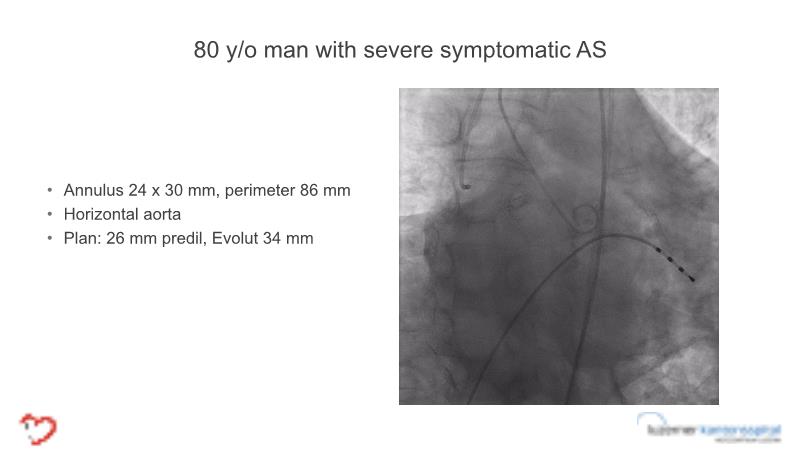

- To learn tips and tricks for managing bicuspid and valve-in-valve interventions